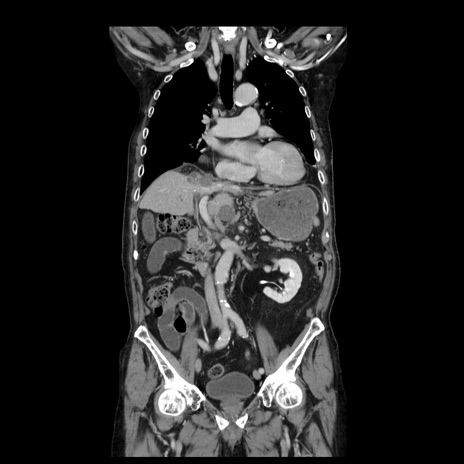

症例21(冠状断像)

【症例】70歳代男性

【主訴】腹痛

【現病歴】肝硬変・肝細胞癌にてかかりつけの方。約9時間前に食後より腹痛出現。症状が徐々に増悪し、嘔吐出現したため来院。

【既往歴】肝硬変、肝細胞癌(RFA、TACE後)

【身体所見】意識清明、表情苦悶様、BT 36℃、BP 129/78mmHg、P 88bpm、SpO2 97%(RA)、右上腹部から心窩部にかけて圧痛あり、反跳痛なし、筋性防御あり。

【データ】WBC 5800、CRP 0.16